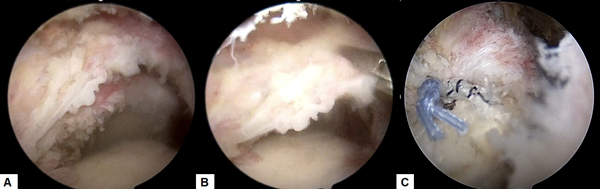

変形性関節症に対する関節鏡手術、人工関節手術も積極的に行っています。とくに肘の関節鏡手術は手術侵襲が小さい割には患者の満足度は高く、慢性的な肘の痛みでお悩みの方は一度ご相談いただければと思います。肩については、近年開発された肩の特殊な人工関節(リバース型)が導入され、変形性肩関節症の方に施行し良好な成績が得られています。

変形性肘関節症の関節鏡所見(左:前方鏡視、中:後方鏡視、右:肘関節内遊離体)

黄三角部:軟骨が線維化し毛羽立っています

A: 腱板断裂部(上に見えているのが断端。下に上腕骨が見えている(黒丸部)。)

B: 断裂部を鉗子(右上)で牽引している。

C: 特殊な糸を用いて断裂部を上腕骨に縫着した(左側に青と白黒縞模様の糸による結び目が見えている)。